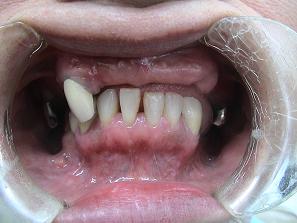

1.

術前のお口の状態です